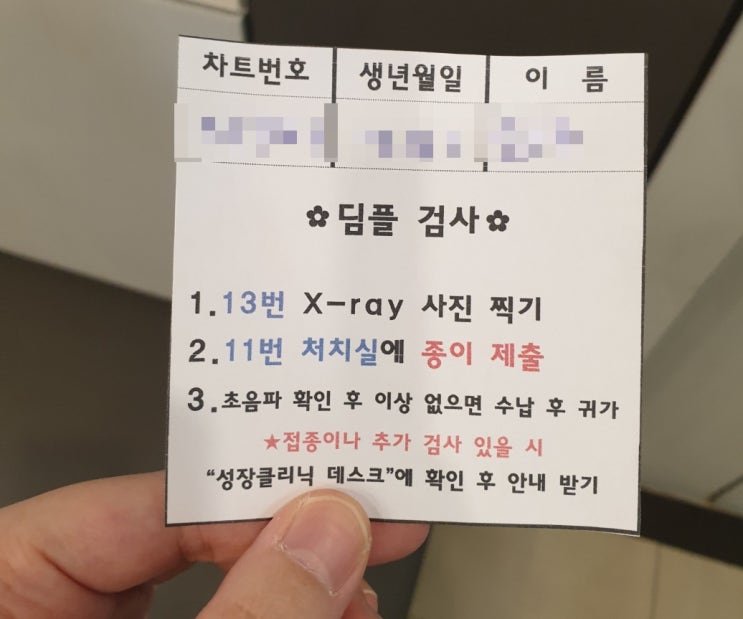

예약을 안 했기에 당직 선생님이셨던 대표 원장님께서 진료를 해주셨어요. 피비침이 일주일째 소량으로 나오고 있다고 말씀드리자 배에 통증은 없냐고 하셨고 약한 생리통 느낌으로 있다고 말씀드리니 일단 경부길이부터 재보자며 질초음파를 봤어요.

경부길이는 3.72! 선생님께서 이어서 배 초음파도 보자고 하셔서 뱃속에 있는 햇살이도 잘 봤는데 꽤 심각한 얼굴로 설명을 하셨어요.

보통 피비침은 전치태반이거나 피고임 등 여러 원인이 있을 ...